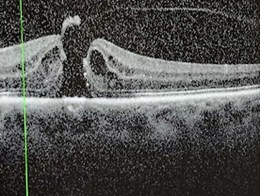

Assessment in the surgical retina clinic revealed a macular hole with cataract and Figure 3 shows their preoperative macula optical coherence tomography (OCT) scan. The patient was promptly placed on the surgical waiting list and underwent vitrectomy with internal limiting membrane peel, C2F6 gas tamponade, phacoemulsification with intraocular lens insertion and retinopexy.

Figure 3: OCT scan of macular hole preoperatively [3].